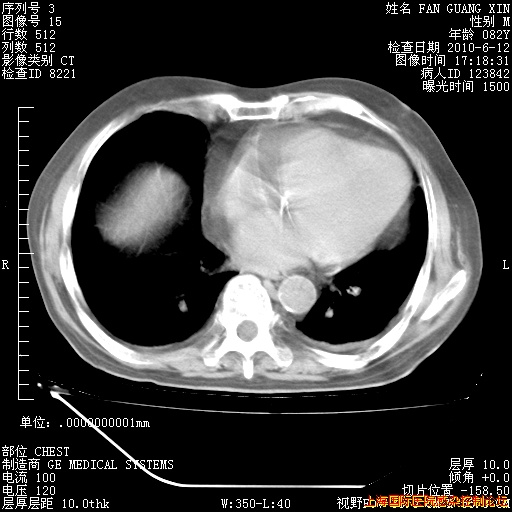

6月12日纵膈窗

整整相隔30天的肺部CT好像有所好转啊。甲强龙减量第3天,需要观察体温。